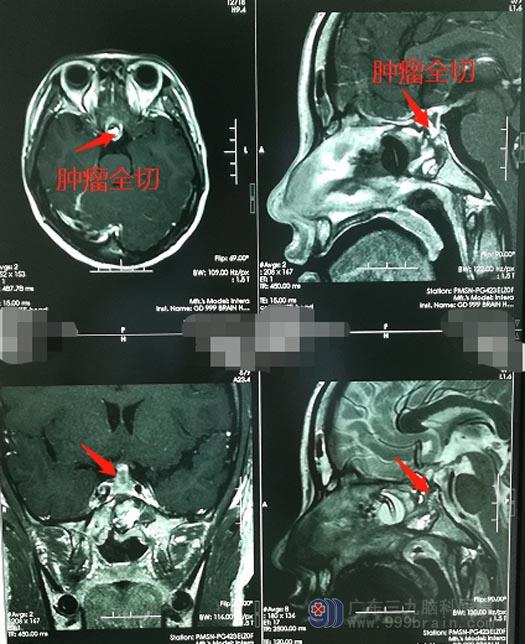

小陈具有明显的手术指征,家属也同意手术治疗,完善术前准备后,由医院副院长、神经外五科主任鲁明主刀“行鞍区占位切除术”,使用内镜经鼻蝶方式,术中磨除蝶窦前壁及鞍底骨质,纵行剪开垂体,可见肿瘤组织,位于鞍内及垂体柄除,质地韧,鱼肉状,术中冰冻病理考虑生殖细胞瘤,继续切除部分肿瘤送检。术后病理结果显示鞍区生殖细胞瘤。

生殖细胞瘤是一种恶性肿瘤,但治愈率较其它恶性肿瘤高,属低度恶性肿瘤。肿瘤长在脑部垂体,会影响生长发育,必须尽早手术切除并化疗。鲁明成功为小陈精准切除肿瘤并保留了全部垂体。生殖细胞瘤对放射线非常敏感,手术后,小陈还要进行继续的放化疗。